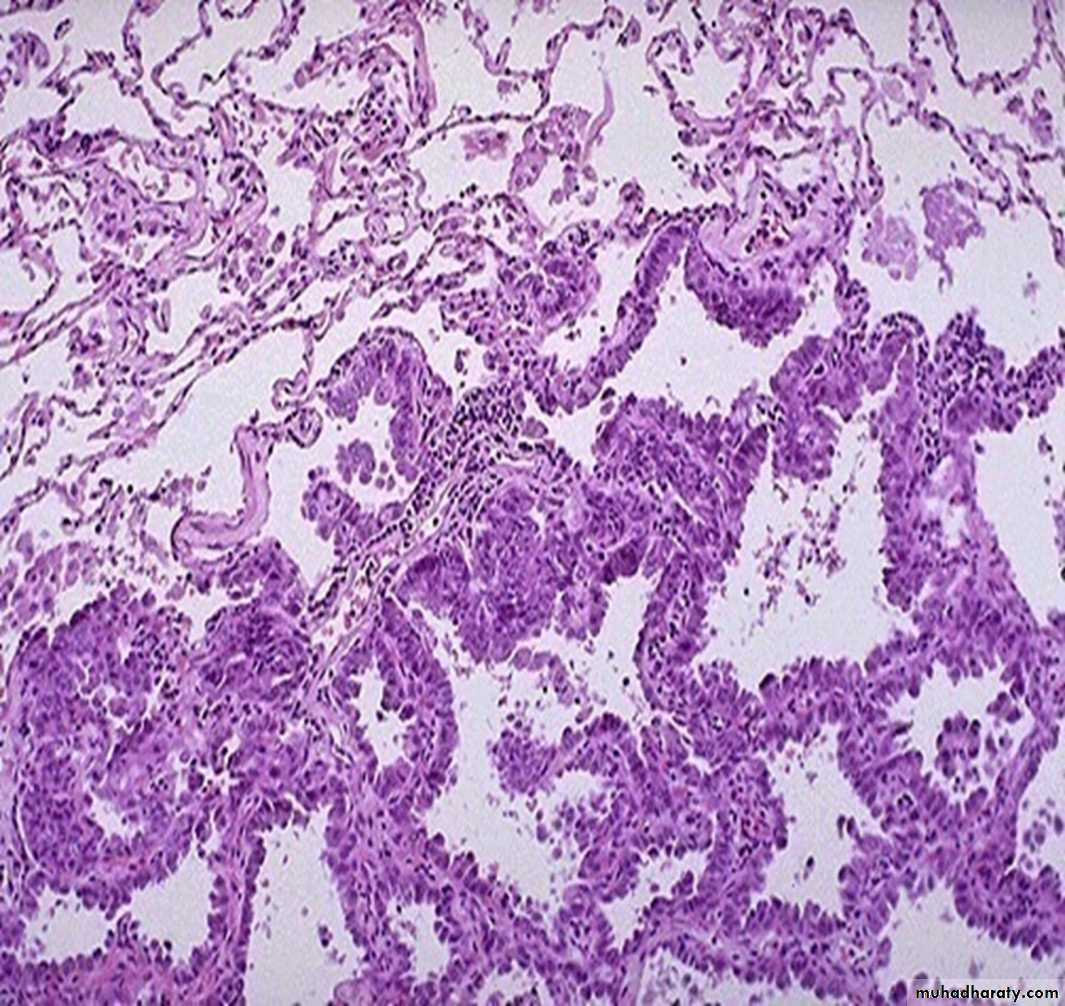

Histologically:

They assume a variety of forms, including acinar (gland forming), papillary, and solid types.Bronchiolo-Alveolar Carcinoma-A type of adenocarcinoma that arises from the bronchiolo-alveolar regions Forms single or multiple nodule(s) which may coalesce to produce pneumonia- like consolidation

Morphology:

solid, glistening, and mucoid, reflects a diffusely infiltrating tumor

atypical cuboidal to lowcolumnar cells proliferating along the existing alveolar walls